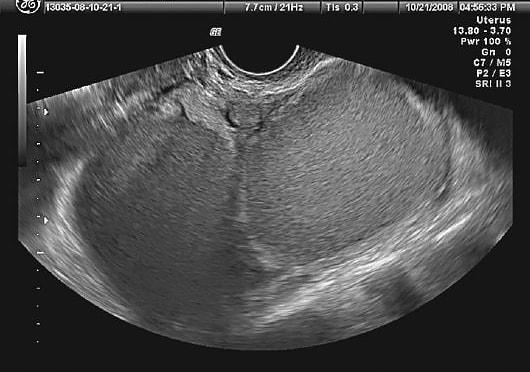

Современные ультразвуковые методы наиболее точно показывают наличие кист. Важно оценить их размеры, количество и глубину расположения. В зависимости от фазы менструального цикла размеры образований могут значительно варьироваться. При проведении томографии картина поражения становится более ясной. Тем не менее, самым информативным методом остается лапароскопия. Это миниинвазивная, но все же хирургическая процедура. Решение о том, какие диагностические процедуры проводить, принимает сама женщина после получения полной информации о преимуществах и недостатках каждого метода.

Диагностика обычно начинается с медицинского осмотра и обсуждения симптомов. Врач может назначить ультразвуковое исследование или МРТ для визуализации яичников и выявления кист. В некоторых случаях может потребоваться лапароскопия для подтверждения диагноза и оценки степени заболевания.